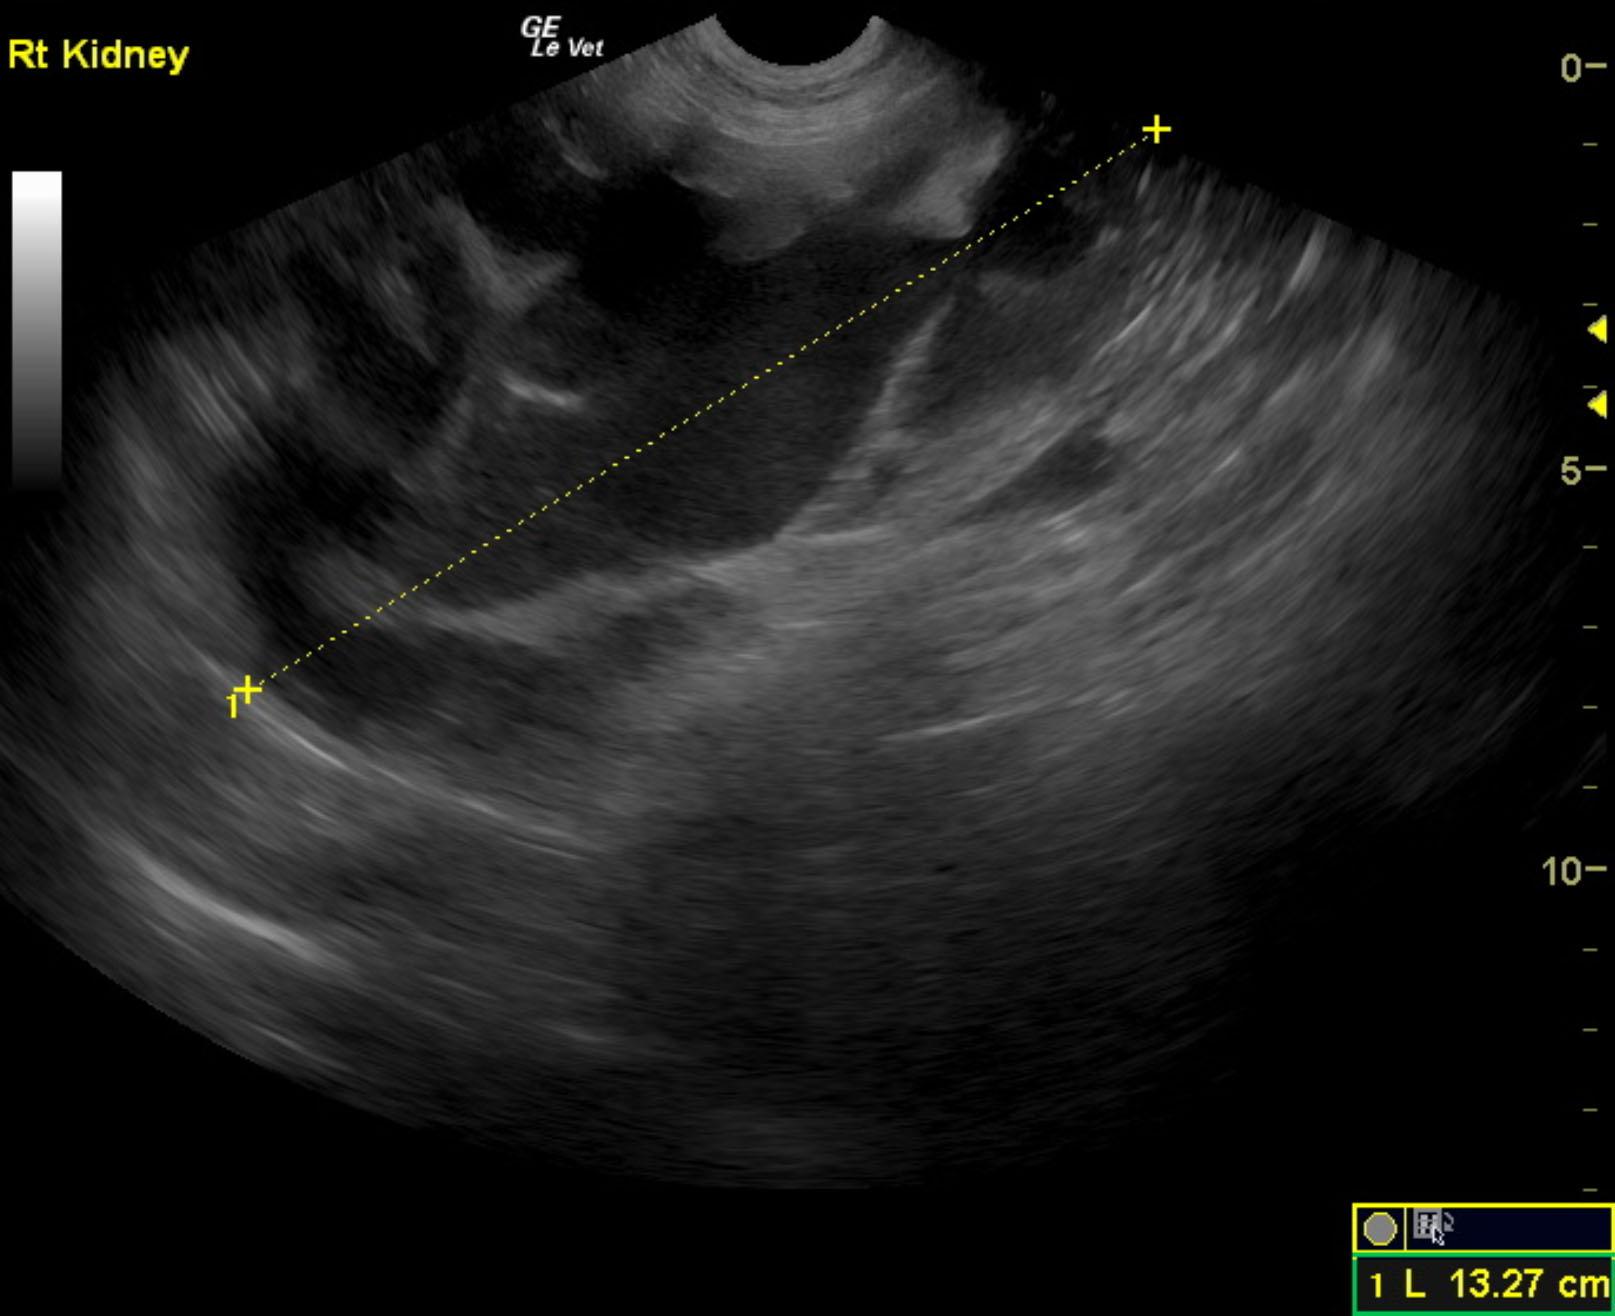

A 3-year-old neutered male Labrador Retriever dog was presented for evaluation of decreased appetite, possible polyuria and polydypsia, taking longer to urinate than normal, and hematuria. On urinalysis, isosthenuria (1.016), 3+ protein, white blood cells, and red blood cells were present. Stress leukogram was evident on CBC, but serum chemistry was within normal limits.

A 3-year-old neutered male Labrador Retriever dog was presented for evaluation of decreased appetite, possible polyuria and polydypsia, taking longer to urinate than normal, and hematuria. On urinalysis, isosthenuria (1.016), 3+ protein, white blood cells, and red blood cells were present. Stress leukogram was evident on CBC, but serum chemistry was within normal limits.